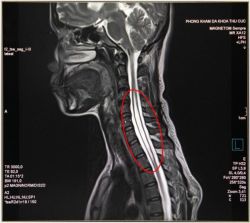

Đây có thể là biểu hiện của nhiều bệnh lý thần kinh như:

Thoát vị đĩa đệm

Thoái hóa cột sống

Hẹp ống sống

Gai đôi cột sống

Rỗng tuỷ,…

Các bệnh lý này tuy không gây nguy hiểm đến tính mạng nhưng có thể làm suy giảm khả năng vận động, ảnh hưởng tới công việc, chất lượng công việc và có thể gây tàn phế suốt đời sẽ tạo gánh nặng cho gia đình và xã hội.